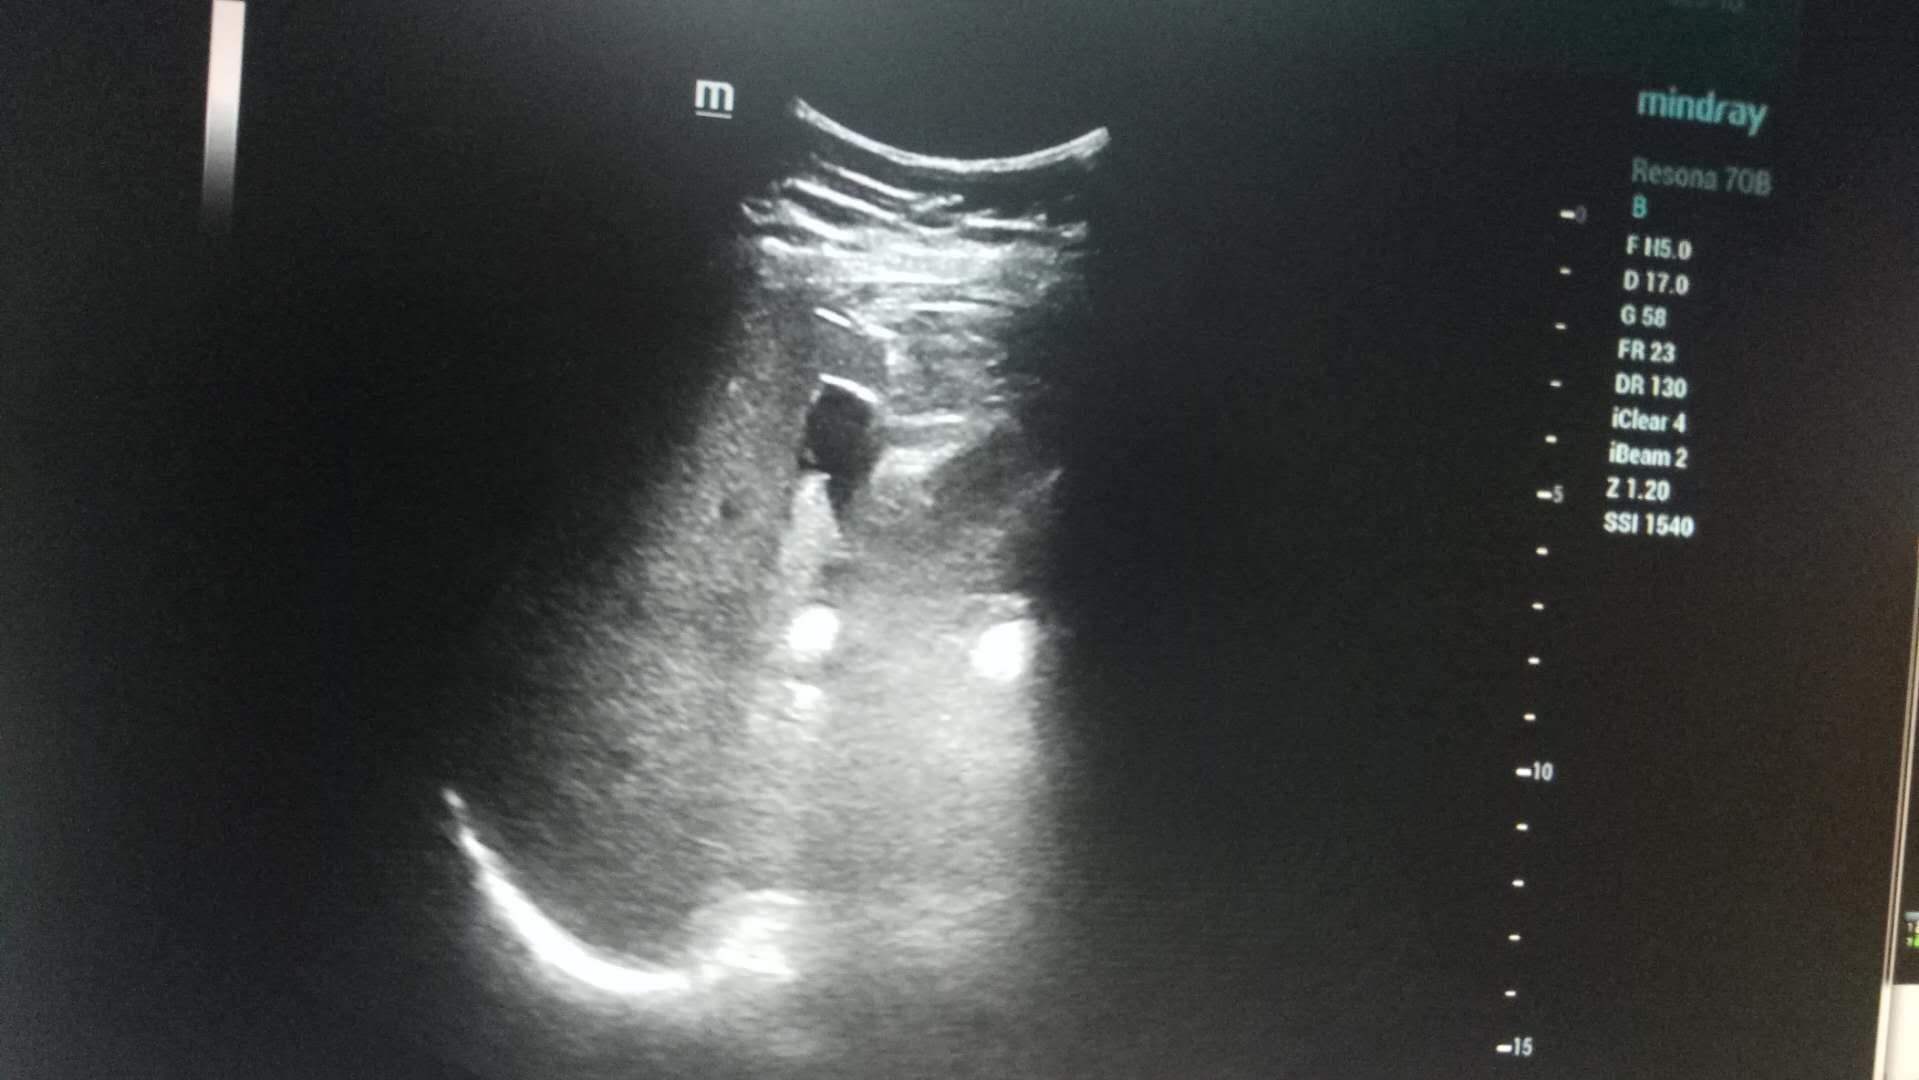

近日,啄木鸟 超声科在高陵区医院成功开展了一例超声引导下肝囊肿抽吸硬化治疗术。患者前段时间查出肝囊肿,因开腹手术风险性大且痛苦,遂联系了高陵区医院超声科,在啄木鸟 超声科主任展小军与对口支援医生杨艳秋的紧密配合下,短短30分钟,通过一根穿刺针,直径近7cm的肝囊肿就被完全抽吸硬化完毕,患者生命体征平稳,休息几小时后已活动自如。

超声介入微创诊疗技术是在实时超声的监视和引导下,完成各种穿刺、活检以及抽吸、插管、注药治疗等操作,达到与外科手术相当的效果,具有创伤小、恢复快、无辐射、介入治疗定位精确等优点。可治疗全身各部位囊肿,尤其是巧克力囊肿效果更佳,还有全身各部位肿瘤的活检和治疗,超声引导下微创治疗是未来医学发展方向。